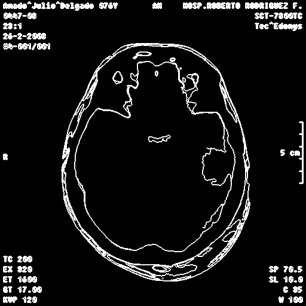

An example of an applications of our proposed strategy to a medical image is shown in Figure 7. In this case, we used different values of and in the . This is a preliminary result. A deeper paper about these results will be published.